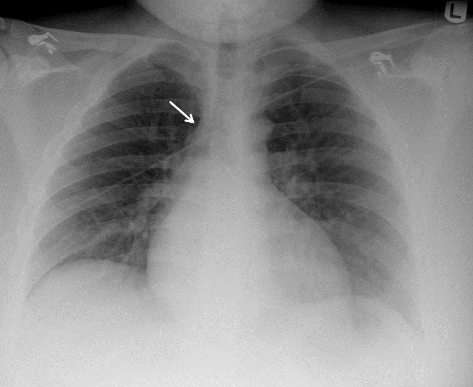

【正常な傍気管線の画像】

下のレントゲンの黄色の矢印で挟まれた線が傍気管線である。